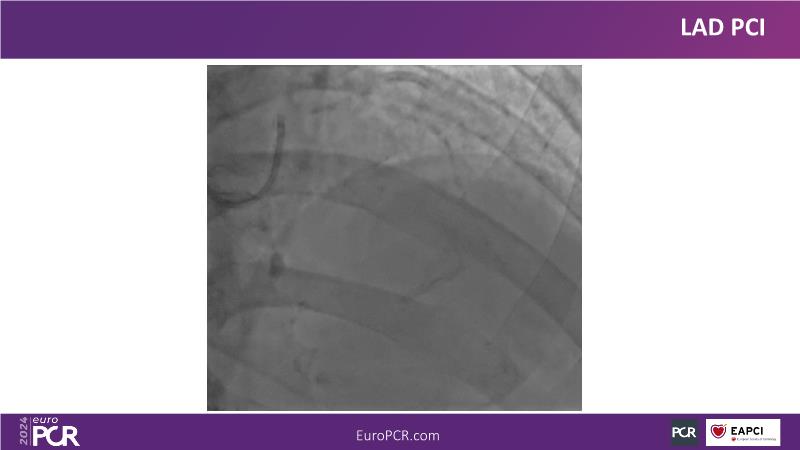

Explore this session to uncover the common association between calcium and acute coronary syndrome, and how intravascular lithotripsy (IVL) offers a safe solution for calcified lesions, with comparable procedural success rates. However, note that ACS cases involving calcium may lead to higher major adverse cardiac events (MACE). Special attention is warranted for women due to their propensity for adverse outcomes. Discover how the C2 + IVL catheter enhances procedural flexibility, yet high intracoronary imaging rates did not yield differences in MACE. Additionally, learn about the potential role of IVL in treating in-stent restenosis (ISR).

- To share clinical experience to uncover practical tips and techniques for intravascular lithotripsy in complex calcified lesions